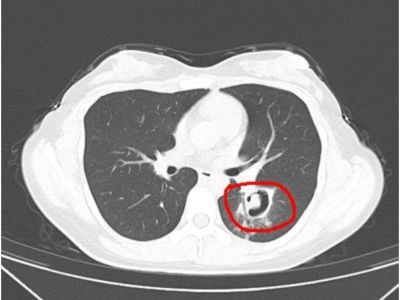

整理发霉衣柜患上肺炎?长沙此前也有类似患者 长沙此前也有类似患者,预防霉菌滋生医生有话说潇湘晨报记者梅玫长沙报道近日,杭州一位市民在整理衣柜时,吸入了一些灰尘和杂质,不久后她开始咳嗽、发热。经查,她气道壁上缀着大量白色菌斑,化验后确认是曲... 新闻资讯